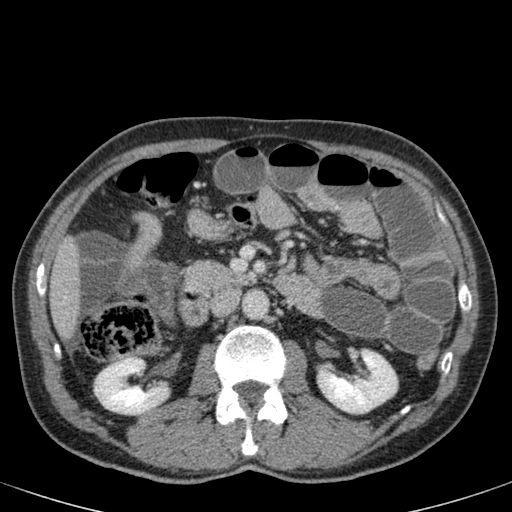

Đây là một bệnh nhân bị tắc ruột non.

Cuộn qua các hình ảnh.

Bạn có thể tìm thấy quai kín và nguyên nhân gây ra nó không?

Khi tiếp nhận bệnh nhân tại phòng cấp cứu với biểu hiện nghi ngờ tắc ruột non (SBO), điều quan trọng nhất chúng ta cần làm, ngoài việc chẩn đoán xác định, là xác định sự hiện diện hay vắng mặt của tình trạng thắt nghẹt.

CT là phương pháp chẩn đoán hình ảnh được lựa chọn trong đánh giá bệnh nhân nghi ngờ tắc ruột non.

Hình ảnh CT của tắc ruột non dạng quai kín phụ thuộc vào hai yếu tố:

- chiều dài đoạn ruột tạo thành quai kín

- hướng của quai ruột so với mặt phẳng tạo ảnh

Nếu quai kín ngắn và nằm trong mặt phẳng tạo ảnh, chúng ta sẽ thấy quai ruột hình chữ U hoặc chữ C.

Một hình ảnh quan trọng khác của tắc ruột dạng quai kín là các quai ruột non giãn xếp theo hình nan hoa với các mạch máu mạc treo hội tụ về một điểm trung tâm.

Hình ảnh này hầu như luôn do xoắn ruột non gây ra.